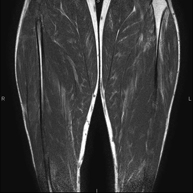

- RM Muslo

Exploración ideal para el estudio de lesiones en músculos isquiotibiales y cuadriceps, frecuentemente lesionados en deportistas. También permite una buena valoración de tendones y nervios periféricos. Tiene una duración aproximada de 20 minutos. No emplea radiación ionizante.